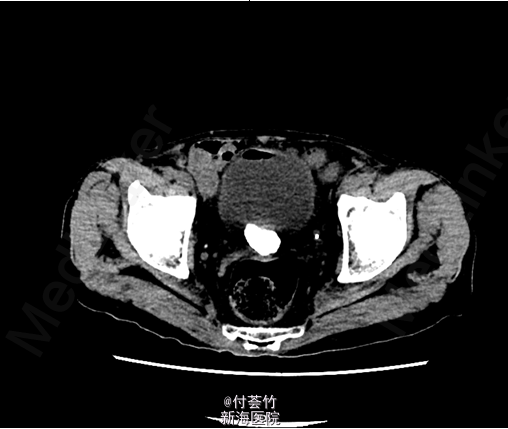

双肾区无红肿、隆起,无叩痛,双侧肋脊点、肋腰点无压痛。腹平软,双侧上中输尿管点无压痛,膀胱区无压痛。双侧腹股沟区未触及肿物 入院后查双肾CTU:膀胱结石,慢性膀胱炎,膀胱少许积气;左肾下部病灶,考虑良性病变,复杂囊肿可能大;双肾多发囊肿;前列腺电切术后改变,残留前列腺钙化